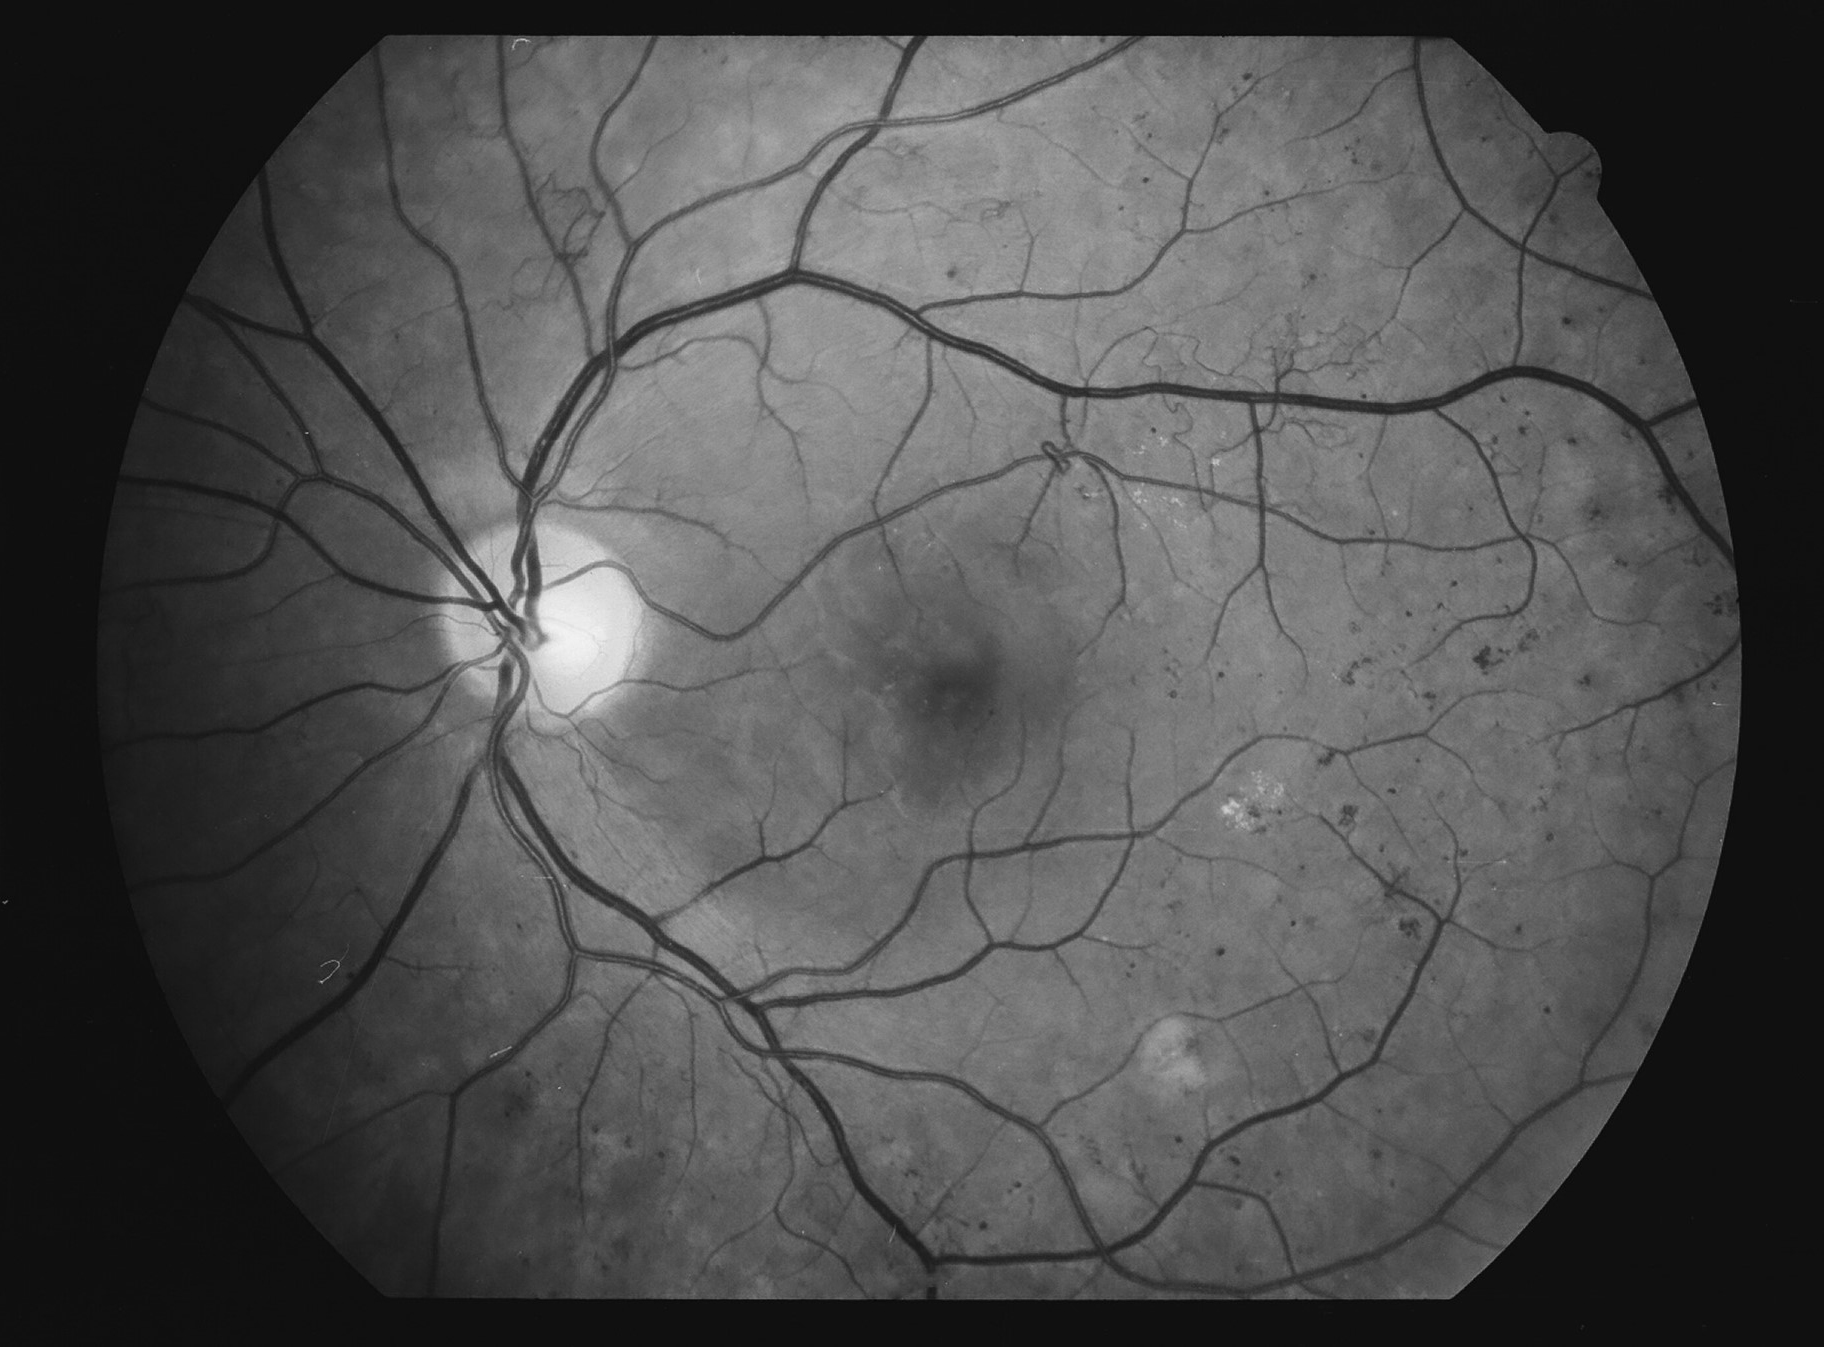

Kuva 2.

Diabetes, taustaretinopatia, oikea silmä. Mikroaneurysma ylätemporaalisen suonikaaren yläpuolella.

Kuva 3.

Diabetes, taustaretinopatia, vasen silmä. Mikroaneurysma makulan ylänasaalireunalla.